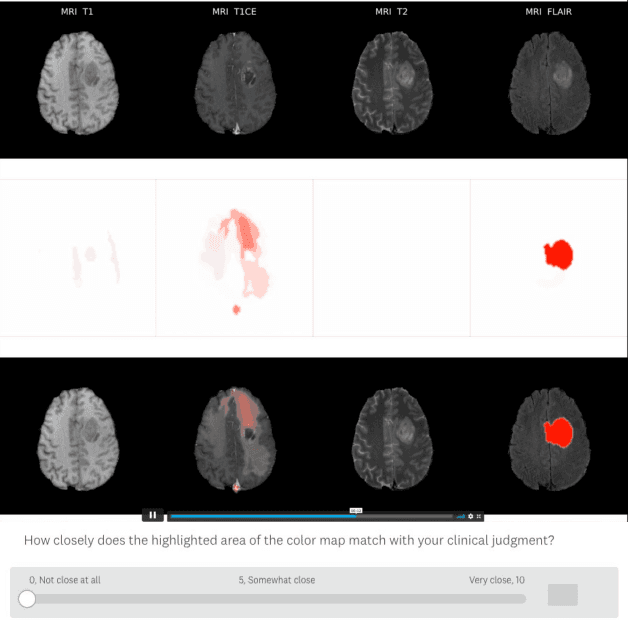

Being able to explain the prediction to clinical end-users is a necessity to leverage the power of artificial intelligence (AI) models for clinical decision support. For medical images, a feature attribution map, or heatmap, is the most common form of explanation that highlights important features for AI models' prediction. However, it is unknown how well heatmaps perform on explaining decisions on multi-modal medical images, where each image modality or channel visualizes distinct clinical information of the same underlying biomedical phenomenon. Understanding such modality-dependent features is essential for clinical users' interpretation of AI decisions. To tackle this clinically important but technically ignored problem, we propose the modality-specific feature importance (MSFI) metric. It encodes clinical image and explanation interpretation patterns of modality prioritization and modality-specific feature localization. We conduct a clinical requirement-grounded, systematic evaluation using computational methods and a clinician user study. Results show that the examined 16 heatmap algorithms failed to fulfill clinical requirements to correctly indicate AI model decision process or decision quality. The evaluation and MSFI metric can guide the design and selection of XAI algorithms to meet clinical requirements on multi-modal explanation.